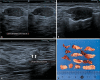

Figure 2

Patient with a core biopsy diagnosis of a papillary lesion, subsequently submitted to VAE. A: Pre-excision ultrasound showing the target lesion. B: Ultrasound during the procedure, showing the positioning of the needle below the lesion and activation of the vacuum. C: Post-excision ultrasound showing the clip marking the biopsy site (arrows). The histological result was consistent with intraductal papilloma with a focus of atypical epithelial proliferation, measuring 3.5 mm, demonstrating the presence, by quantitative criteria, of intraductal papilloma with low-grade ductal carcinoma in situ.